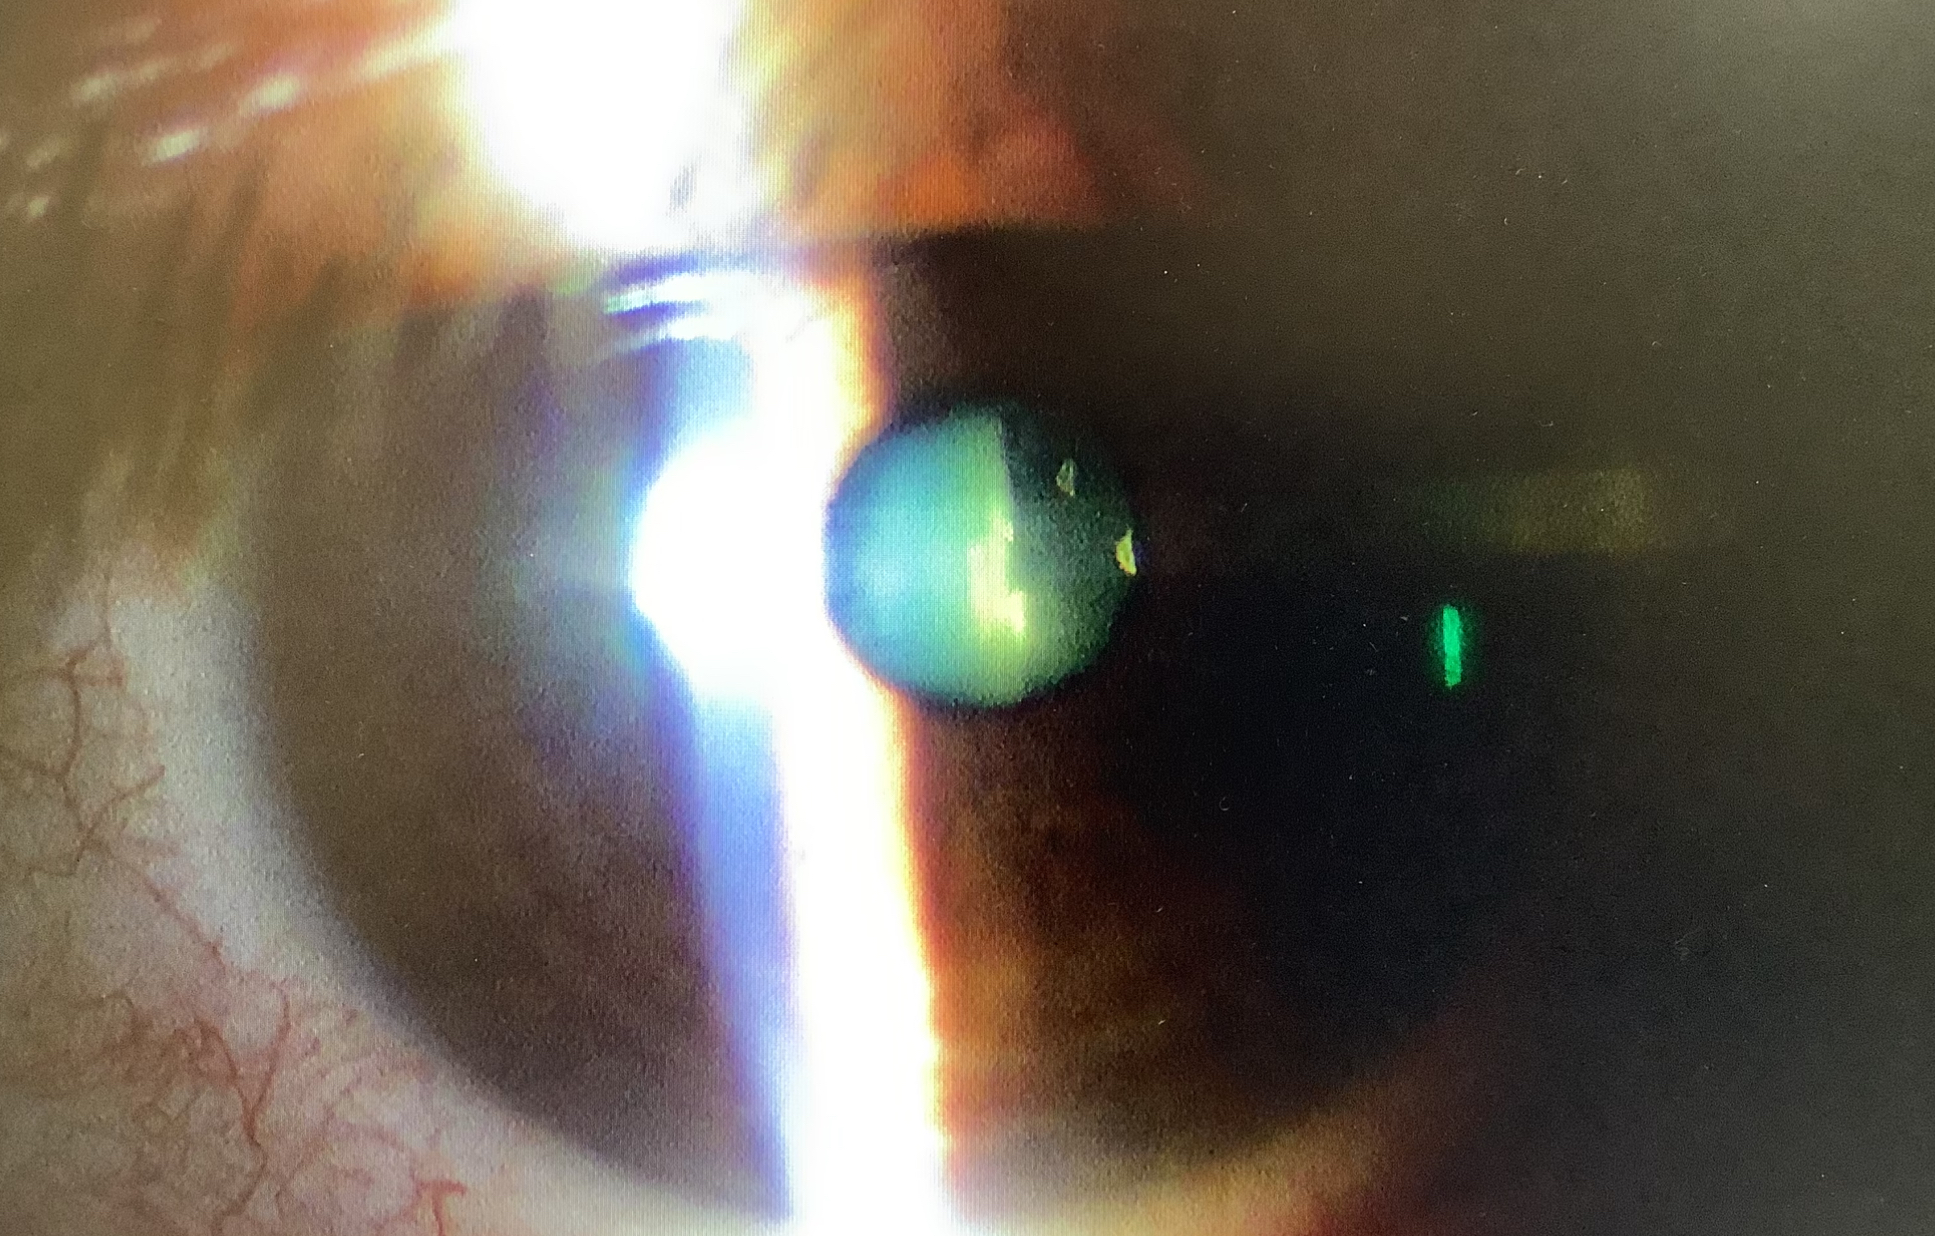

手術の申し込みは、白内障3人、眼瞼下垂1人、硝子体手術1人でした。

今日の手術は、白内障10件、黄斑上膜の硝子体手術1件、眼内レンズ交換2件でした。